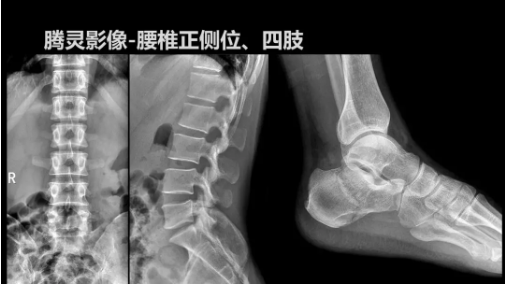

2019年10月19日,82屆秋季CMEF于青島世博城國際展覽中心如期舉辦,國內(nèi)動(dòng)態(tài)DR領(lǐng)域的佼佼者安健科技攜新品——“騰靈”多功能診斷專用動(dòng)態(tài)DR亮相展會(huì)現(xiàn)場。

“騰靈”是安健科技的第四代動(dòng)態(tài)DR產(chǎn)品,可實(shí)現(xiàn)全科室應(yīng)用。如各類常規(guī)的X線檢查、消化道檢查、骨科檢查、婦科、兒科檢查等。此外,安健科技為“騰靈”在真正意義上實(shí)現(xiàn)多科室、多功能診斷進(jìn)行了多項(xiàng)針對(duì)性設(shè)計(jì)。

相較前代產(chǎn)品,“騰靈”在圖像質(zhì)量方面得到了全面升級(jí),“騰靈”采用17*17非晶硅平板探測器設(shè)計(jì),采集矩陣達(dá)3072*3072,動(dòng)態(tài)范圍達(dá)16bit,為成像提供超大視野的同時(shí)保證成像質(zhì)量,此外,該款機(jī)型可根據(jù)醫(yī)療機(jī)構(gòu)的差異化需求而選配不同的動(dòng)態(tài)平板探測器,以此來適應(yīng)不同階層用戶所需。